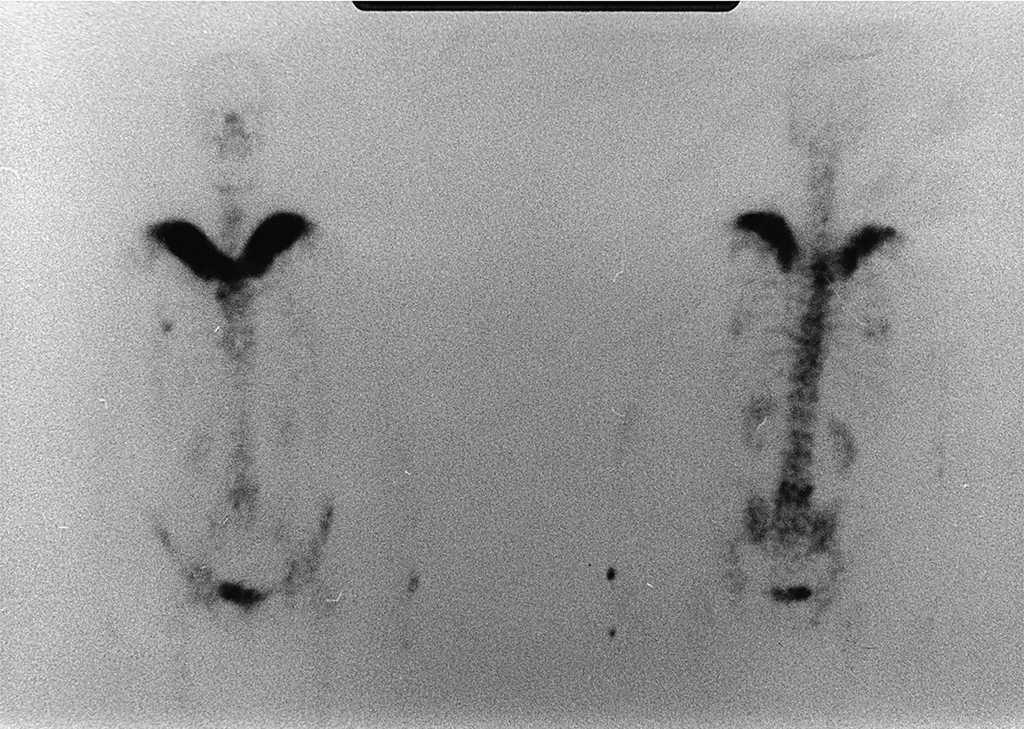

La radiografía simple de tórax (fig. 1) puso de manifiesto unas clavículas difusamente aumentadas de tamaño, con una notable alteración de la arquitectura ósea: las porciones distales mostraban una intensa esclerosis de aspecto algodonoso, mientras que en las proximales predominaba la rarefacción ósea, con trabéculas groseras y desordenadas.

Figura 1. Radiografía simple de tórax: aumento del tamaño de ambas clavículas, con intensa esclerosis de su porción distal y rarefacción ósea en su mitad proximal.